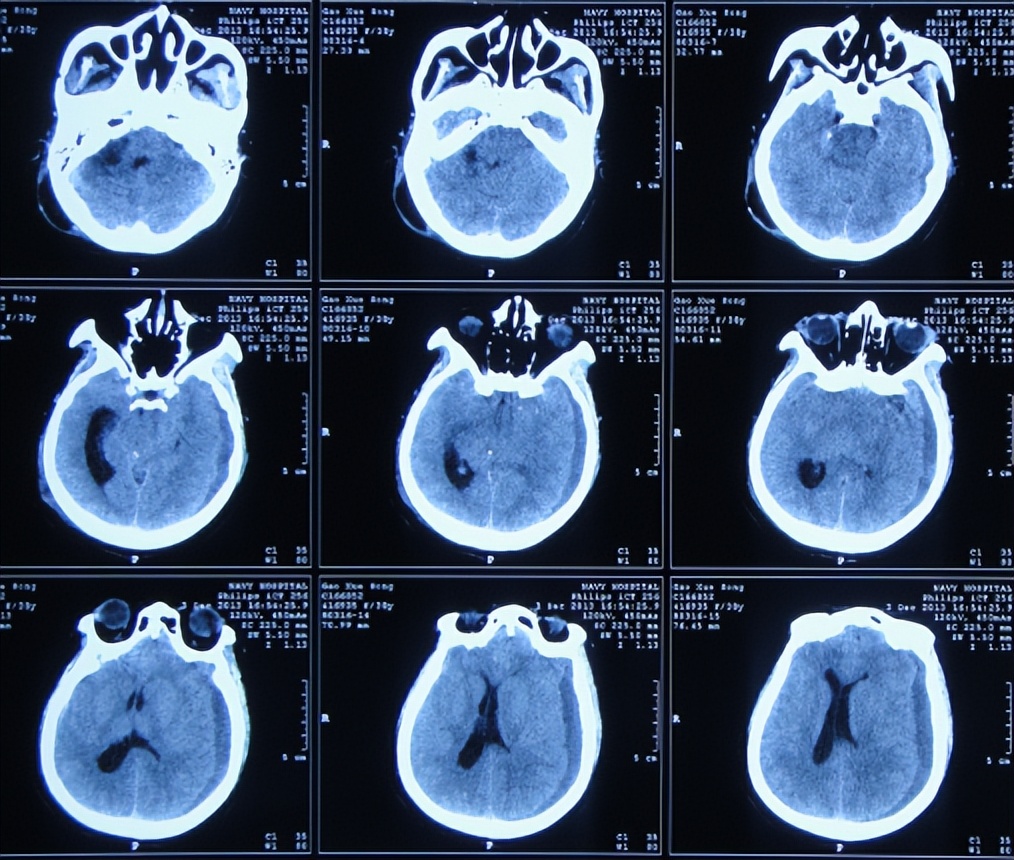

听神经瘤切除术后7天即2013年11月21日,查头颅CT示仍有血肿(图-3),出现发热,最高体温体温38.3 ℃左右,给予腰穿检查脑脊液后认为有感染,给予腰大池引流术及鞘内注射万古霉素。

图-3:2013年11月21日头颅CT